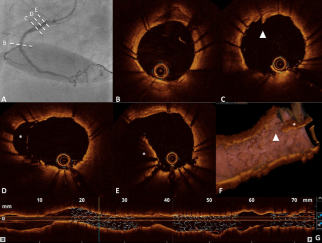

An 80-year-old man with a history of acute inferior myocardial infarction was admitted to our hospital. He had undergone bare-metal stent (3.5/28 mm) implantation in the mid-right coronary artery 22 years prior.

This case highlights that rotational atherectomy is merely paving the road and may help in superficial calcifications. It also showed the useful role of optical coherence tomography (OCT) for guiding the appropriate treatment strategy....